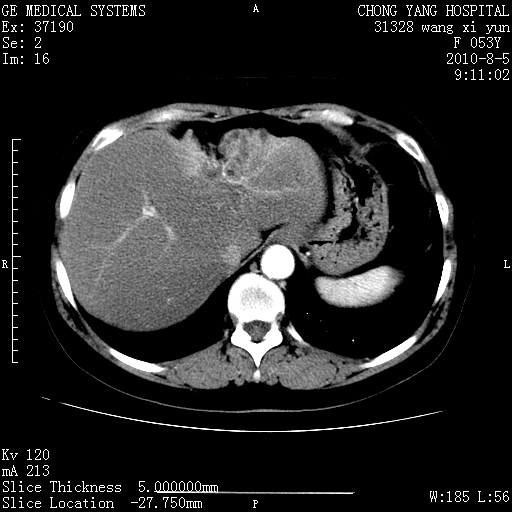

标题: CT28214:F41Y 血尿二十天,建议盆腔平扫加增强。

胆管细胞ca?

1)考虑肝左叶胆管细胞癌。2)脂肪肝。

支持胆管细胞ca。